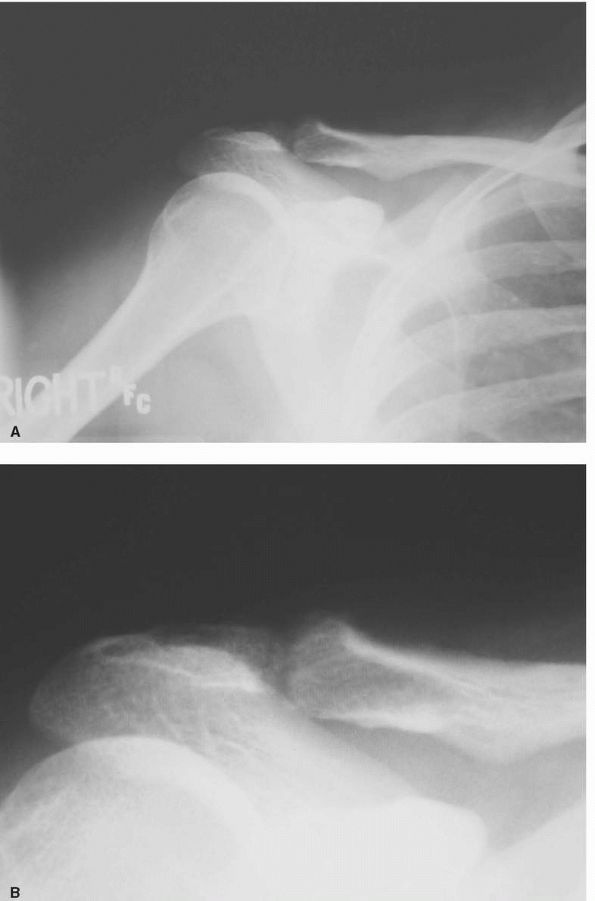

are usually sufficient for initial radiographic evaluation. The Zanca

pathological process. Degenerative disease manifests itself similarly

and sclerosis, and osteophyte formation (Figure 12-2).

In contrast, osteolysis of the distal clavicle may demonstrate relative

osteopenia, widening or tapering of the distal clavicle, and expansion

of the joint space (Figure 12-3).